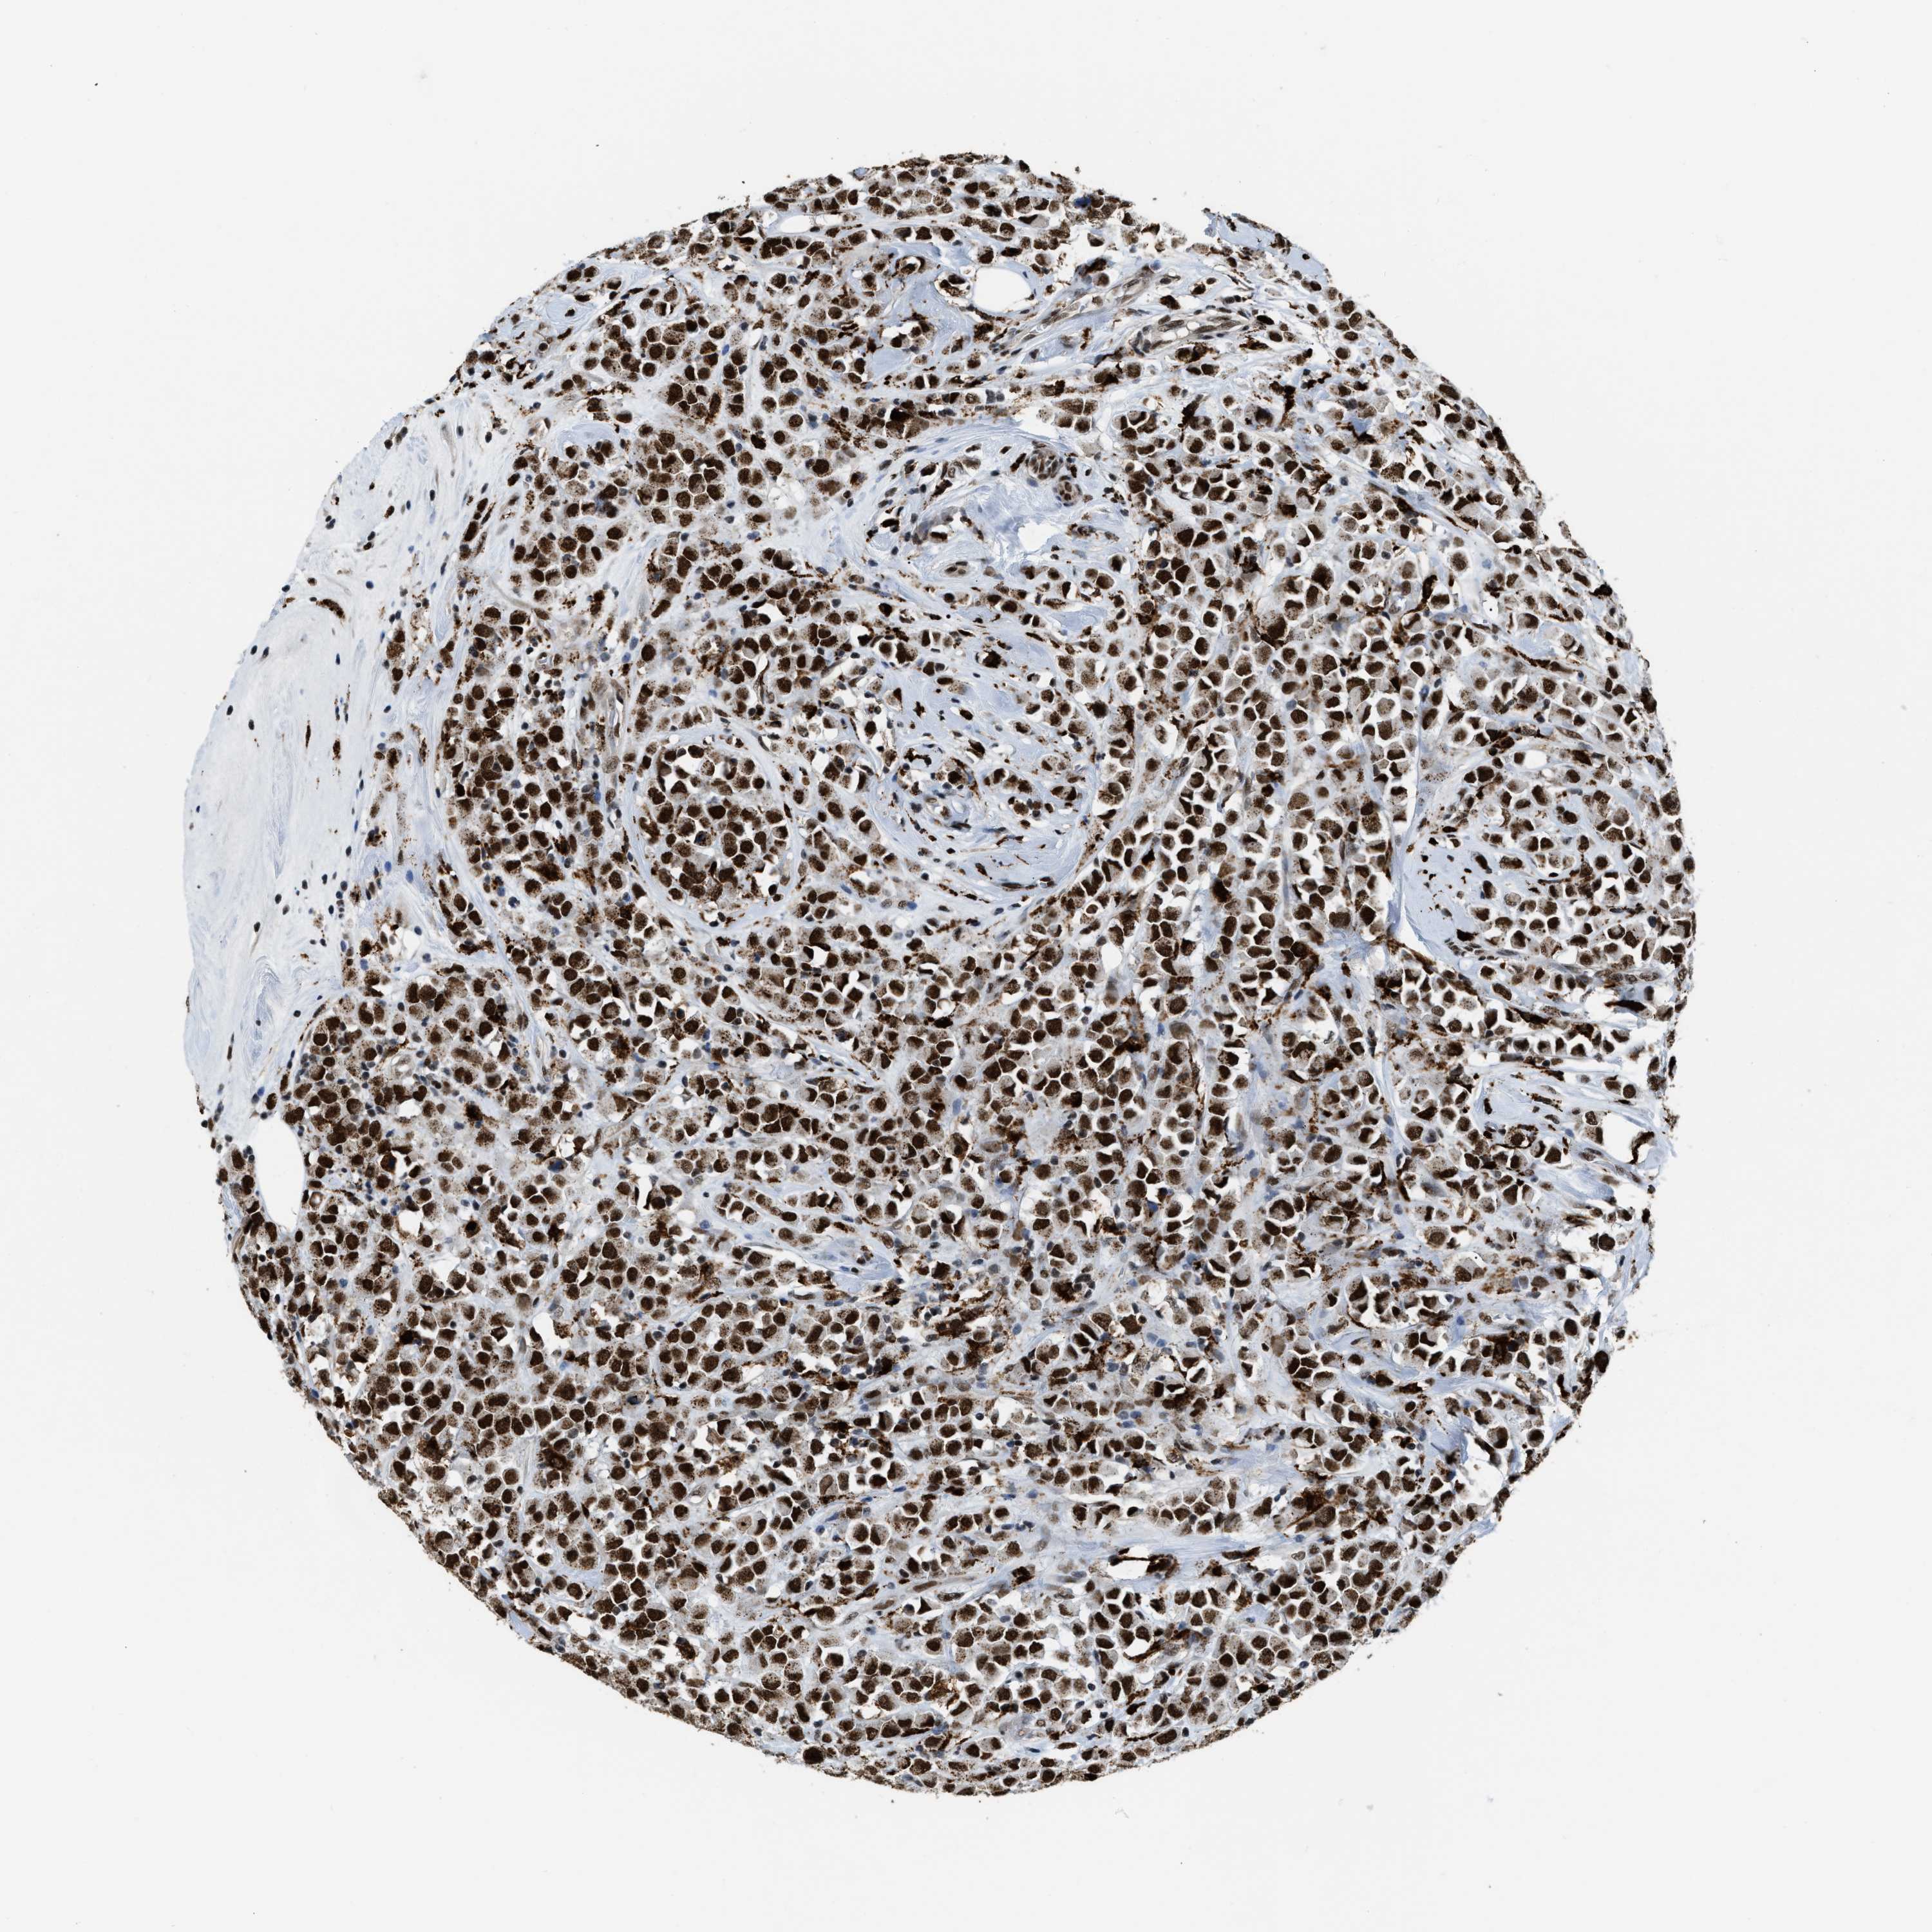

CANCER BREAST CANCER Show tissue menu

BRCA TCGA BRCA VALIDATION PROTEIN EXPRESSION

Breast cancer

Human cancer